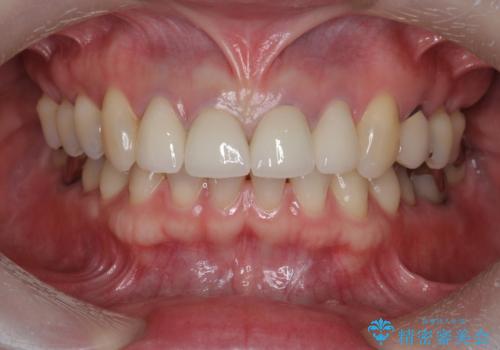

- 44万円(仮歯・ジルコニアクラウン×4)費用は治療当時の料金となります

金属を用いないジルコニアセラミッククラウンは透明感の再現性に優れ、審美性と自然な仕上がりの両立を期待することができます。